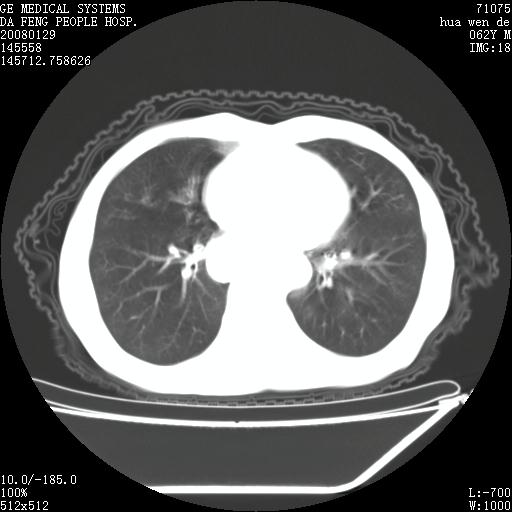

男性,67岁。作肺部检查时发现

理由:1、右上肺内病灶,空洞形成,有液平。

2、肺内多处炎症。

3、前段肺内炎症,支气管引流通畅,与肿块无关系。

1.整个食管扩张,未见明显占位性病变,贲门区亦未见明显占位病变,考虑:贲门失驰缓症;

2.右上肺病变边缘可见毛刺,囊壁厚度不均匀,周围境界较清楚,未见炎性渗出性影,右上肺外带可见片状影,边缘不清,考虑:肺癌伴空洞形成、右上肺炎。

食管全程扩张,壁均匀不厚,喷门失弛缓症

右上肺空洞可见液平,临近肺野磨玻璃密度,考虑1.结核2.脓肿